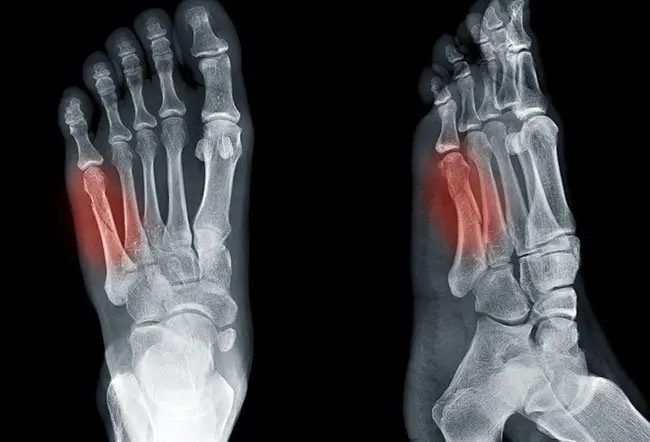

La frattura di Jones è una frattura trasversale che interessa la porzione prossimale del quinto metatarso, precisamente nella giunzione metafisio-diaphisema, escludendo la superficie articolare. Questa frattura coinvolge l’osso lungo del piede situato sul lato esterno e rappresenta una delle lesioni più comuni del piede.

La pseudo-frattura di Jones, invece, coinvolge una linea di frattura più piccola che attraversa la base del quinto metatarso, compresa la superficie articolare, ed è tipicamente riconosciuta come una frattura da avulsione, causata da un distacco parziale del tendine o del legamento.